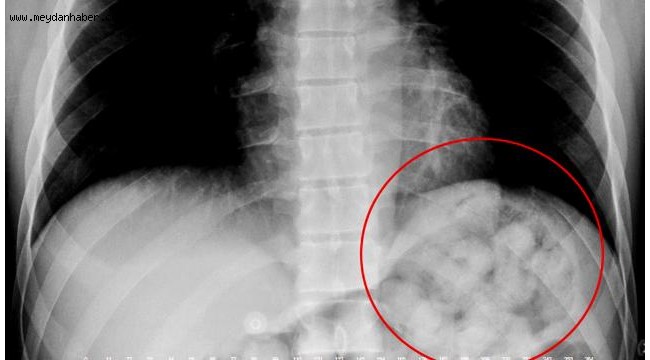

Narziveh'in röntgen filmlerinde midesinde uyuşturucu madde kapsülleri görüldü. Bunun üzerine Narziveh mahkeme kararıyla ameliyata alındı.

Ameliyatın ardından şüphelinin midesinden ikisi patlamış halde 72 kapsül içerisinde yaklaşık 900 gram metamfetamin çıkarıldı.